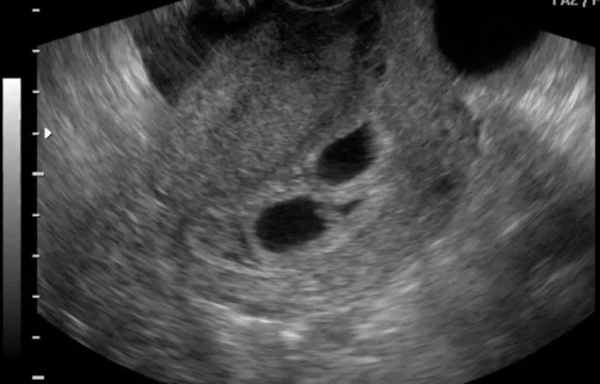

Лучевые признаки дихориальной диамниотической двойни

Дихориальная диамниотическая двойня характеризуется наличием 2 плацент и 2 амниотических оболочек. В данном случае происходит развитие одно- или двуяйцевых двойняшек.

Какие обследования нужно пройти

УЗИ точно подтвердит наличие в матке нескольких эмбрионов уже с 5‒6 недели — на ранних сроках их уже видно, и они выглядят как две (а может быть три или четыре) горошины. Уже на 9‒10 неделе можно определить, есть ли у каждого плода отдельные пузырь и плацента, также доктор прослушивает сердцебиение каждого малыша.

Многоплодные беременности различают по типу плацентации и по количеству амниотических полостей. При беременности дихориальной диамниотической двойней у каждого ребенка есть своя плацента и своя отдельная амниотическая полость, в результате такой беременности рождаются разнополые дети или дети не похожие друг на друга. При монохориальной диамниотической двойне близнецы находятся в отдельных амниотических полостях, но делят одну плаценту на двоих, в результате такой беременности рождаются однополые дети похожие друг на друга как две капли воды.